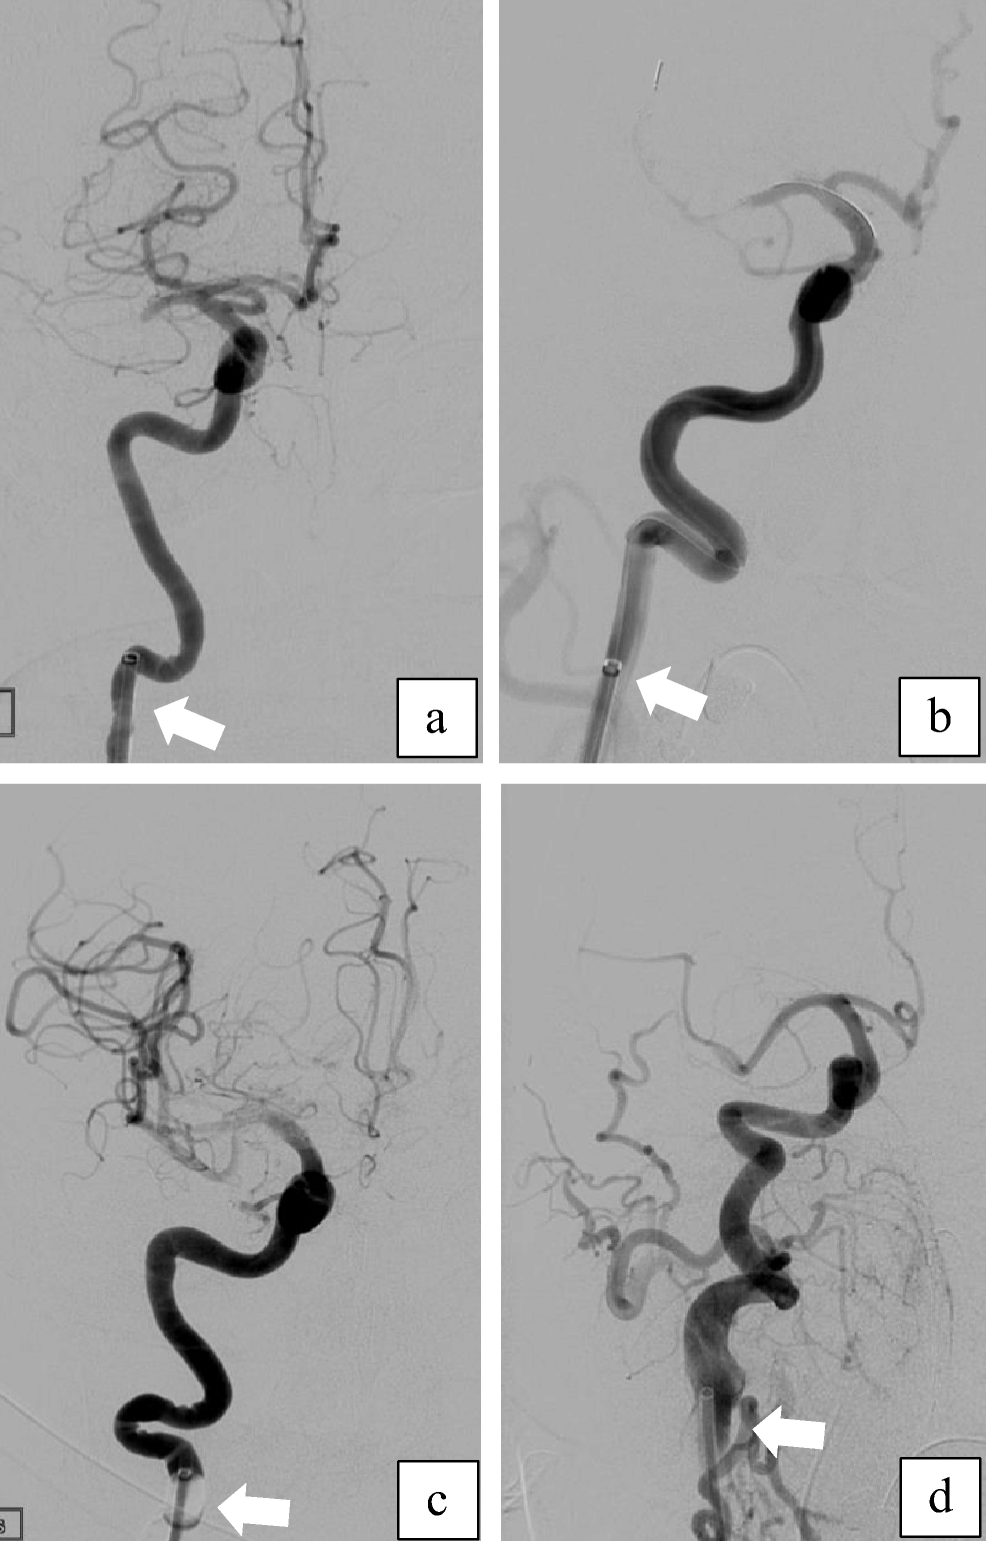

The anatomy of the CoW ipsilateral to the stroke side was determined from the invasive angiographic images on record and correlated with the features of the CTA images to obtain a final evaluation. Variations in diameters between the MCA and the ICA were determined as the ratio of the diameter of the ICA (measured distal to the posterior communicating artery (PCoA) segment) to that of the proximal M1 segment. Elongation of the carotid artery was defined on the basis of such angiographic features as the presence of kinking or tortuosity of the ICA distal to the position of the BGC (Fig. 1), as proposed by Jeong et al. [13]. BGC positioning for treatment was classified into three groups based on dividing the ICA into three segments: (1) the distal ICA (BGC tip located in the distal third of the ICA, i.e., subpetrosal placement), (2) the proximal ICA (BGC tip located in the caudal two thirds of the ICA), and (3) the distal common carotid artery (CCA) (Fig. 2).

Fig. 2

Balloon guide catheter position (BGC) in the carotid artery. From right to left, angiographic classification of BGC location for treatment: dividing the internal carotid artery (ICA) into three segments from the subpetrosal segment to the extracranial bifurcation, the proximal ICA is the caudal two thirds of the cervical carotid. The following two images show distal BGC positioning (a) and proximal BGC positioning (b) in the ICA